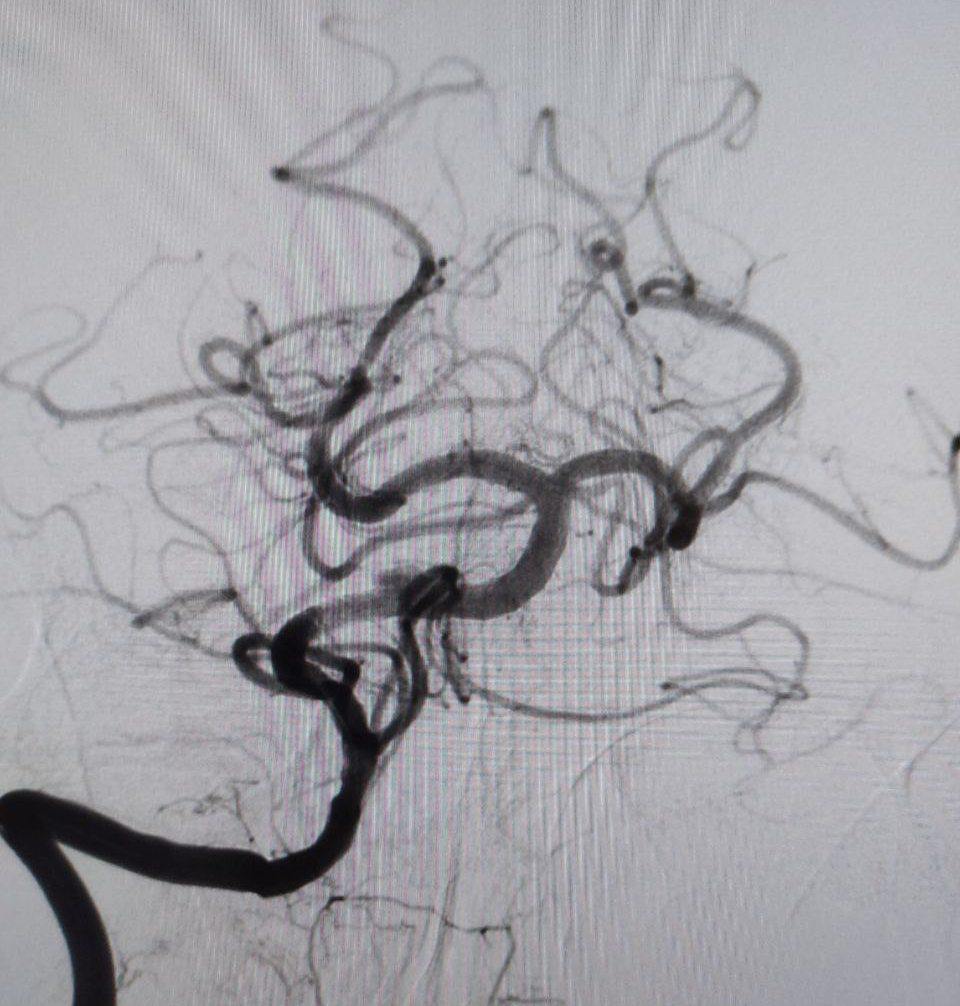

— У пациента был выявлен атеротромбоз — тромбоз на фоне атеросклеротической бляшки — основной артерии, которая обеспечивает кровоснабжение важнейших отделов головного мозга. Это очень тяжелое состояние с крайне высокой летальностью. Операция длилась около часа. После удаления тромба в артерии осталась бляшка, критически суживающая ее просвет: потребовалась имплантации стента. К счастью, мы успели вовремя, и операция прошла успешно, — прокомментировала заведующий центром Элеонора Тулякова.